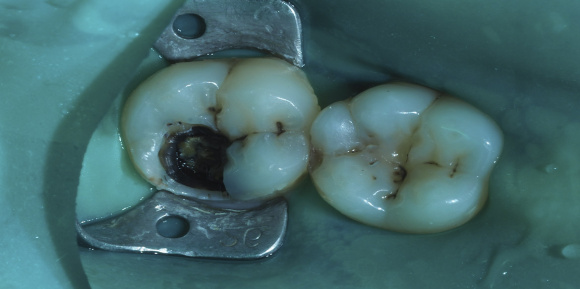

Реставрация зубов